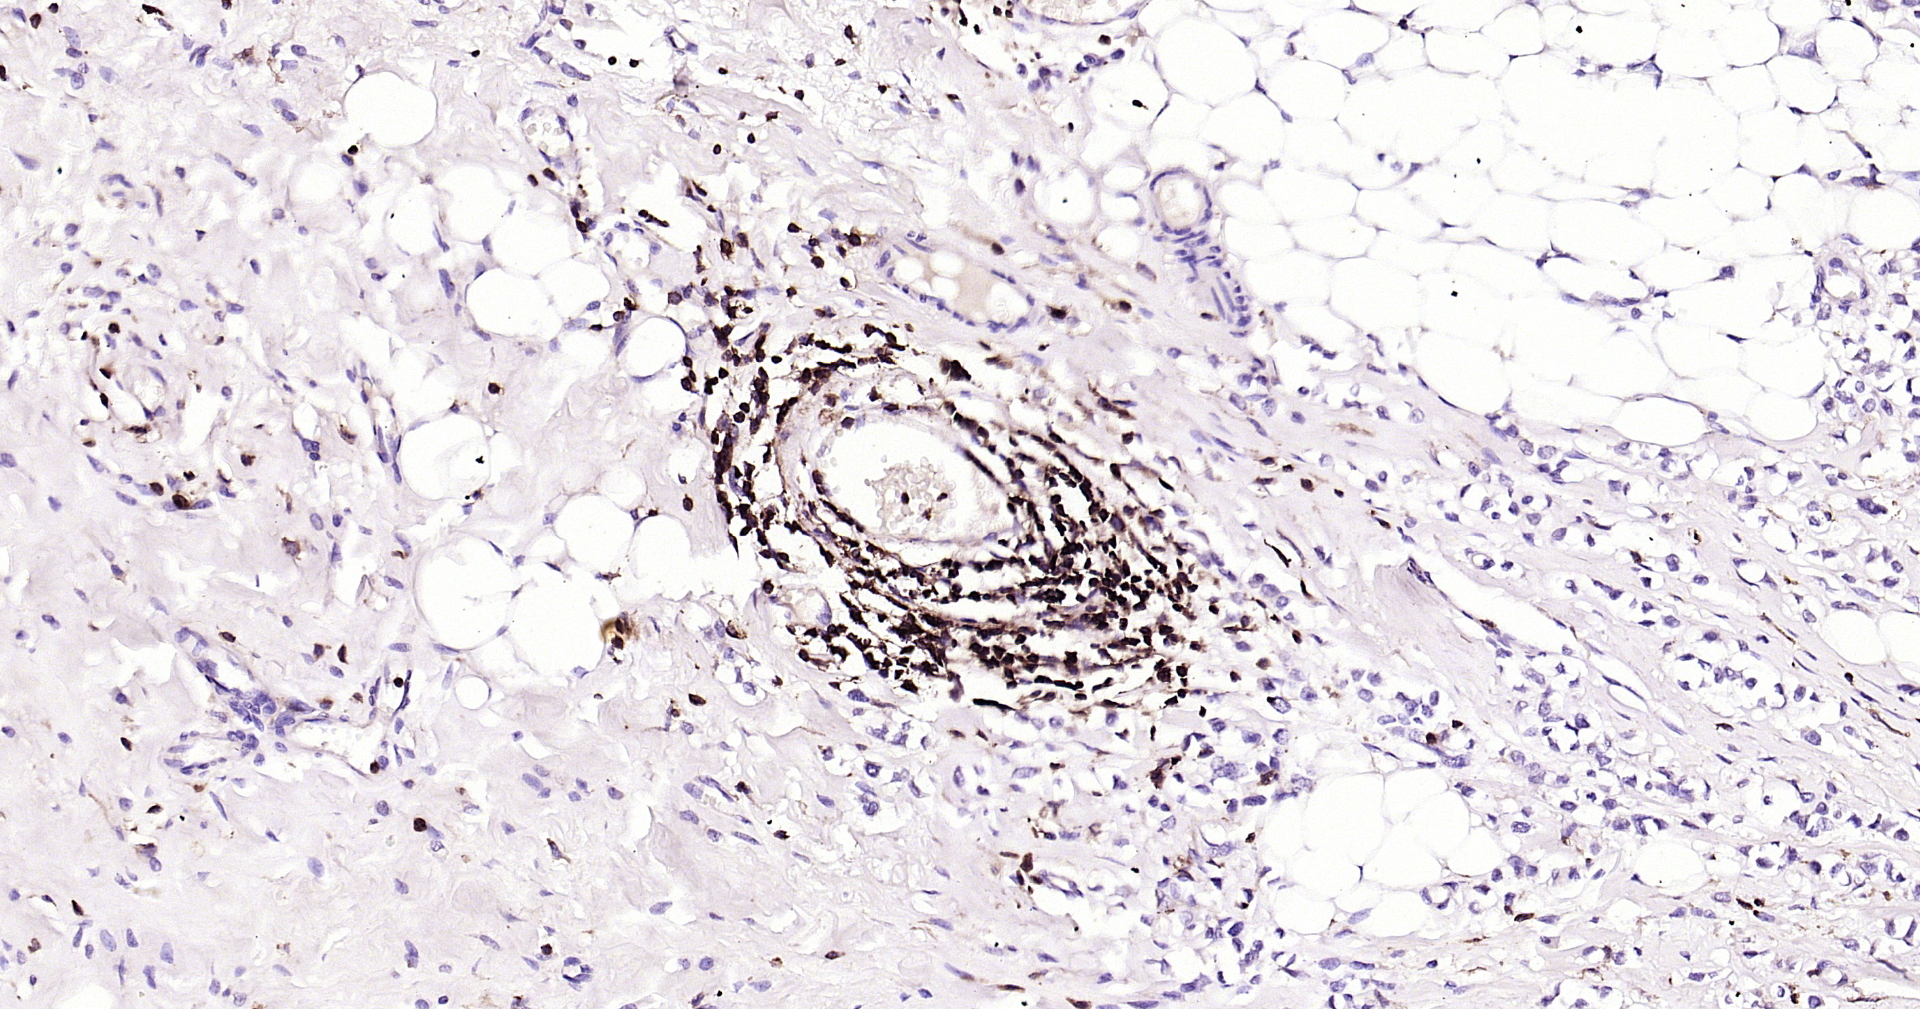

CD45 Recombinant Antibody

• IHC-P

IHC-P IHC-P1:100-500